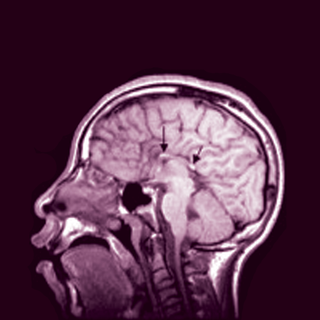

The keto diet claims to force the body into permanent ketosis — a metabolic state characterized by increased levels of ketones, the form of energy the body makes when burning fat stores. Ketones are one of two types of energy the brain uses, the other being glucose. In the keto diet, any food that breaks down primarily into glucose — that is, most carbohydrates and proteins — is highly restricted, while high-fat foods that break down into ketones — butter, fish, eggs, cheese, bacon, avocados — are encouraged.

All of this obscures the real question, however, by confusing weight loss with health. For some people, weight loss may be required for better health. For these people, the keto diet might be helpful — in consultation with a doctor and nutritionist — though lab tests of overweight men suggest keto is no more helpful than other weight loss regimens. The keto diet may also have health benefits for children with severe epilepsy. (Ketogenic diets have actually been known to help control seizures in people unresponsive to epilepsy medication for the past 100 years, proving there’s no new diet under the sun, just re-appropriated ones.) And the keto diet may also be helpful in controlling blood sugar levels (but again, only in consultation with a doctor, because limited research hints that the keto diet might actually cause some people to become more glucose intolerant and contribute to the development of diabetes).